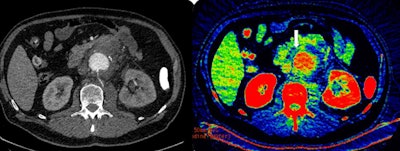

On the left is contrast-enhanced axial CT scan of the abdomen in a patient with suspected rupture of abdominal aortic aneurysm. Leakage of blood from the aorta (center) is not obvious. On the right is the corresponding dual-energy CT scan (iodine map). Concentration of iodine corresponds to gradations of the recolor scale. White arrow indicates high concentration of iodine (yellow-green areas inside the blue nonenhancing tissues) in the blood leaking into the para-aortic tissues from the small contained aortic wall rupture (later confirmed in surgery). Images courtesy of Dr. Valentin Sinitsyn.Sinitsyn's talk will in part focus on the use of dual-energy CT (DECT) for such emergency vascular cases. The technique increases conspicuity of iodine extravasation and intravascular thrombi, and the radiologist often can skip nonenhanced scans and perform only a single contrast-enhanced acquisition with reconstruction of virtual noncontrast images.

"DECT can yield qualitative information similar to MRI and reveal small quantities of iodine in tiny blood leaks in the soft tissue. There is no difference for the patient in terms of time, compared to nonenhanced scans, but it is only available on new generation scanners, less than 1% of all existing CT machines," he noted. "Given that the life span of a machine is eight to 10 years, it will be another decade before we can expect to see DECT routinely applied in acute abdominal emergencies."